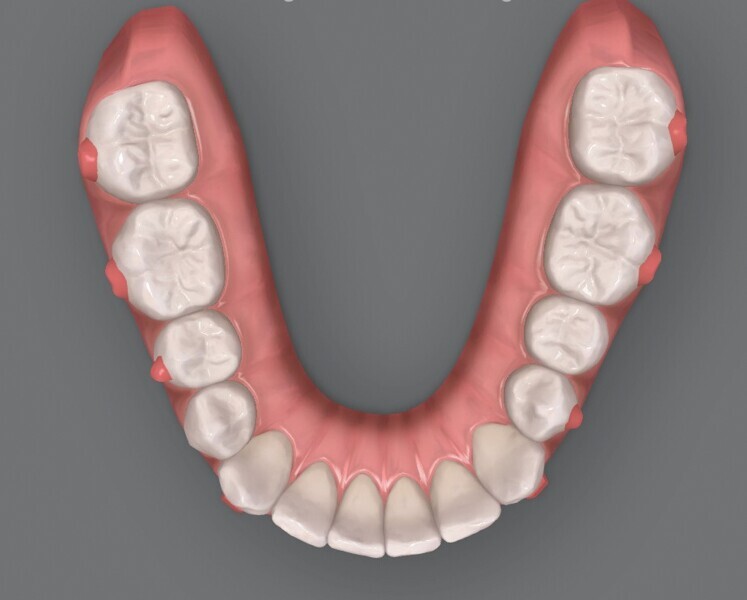

Fig. 4a : Premier résultat prévu par simulation ClinCheck.

Fig. 4b : Premier résultat prévu par simulation ClinCheck.

Fig. 4c : Premier résultat prévu par simulation ClinCheck.

Fig. 4d : Premier résultat prévu par simulation ClinCheck.

Fig. 4e : Premier résultat prévu par simulation ClinCheck.

Le premier plan de traitement par simulation ClinCheck prévoit 53 aligneurs, afin de réaliser une distalisation séquentielle postérieure d’environ 4 mm sur le côté gauche du maxillaire, une expansion de 2 mm par quadrant et un alignement dans la zone antérieure. Il prévoit également une réduction interproximale (RIP) sélective de 0,25 mm sur chaque face des dents de l’arcade mandibulaire, et de 0,10 mm à 0,15 mm pour les dents de l’hémiarcade maxillaire droite (Fig. 4). Une application topique de fluorure est planifiée dans les zones soumises à une RIP après la procédure. Des élastiques de classe II sont utilisés du côté gauche pour faciliter la distalisation. La fréquence de changement des aligneurs est fixée à sept jours et elle sera ramenée à cinq jours par la suite. Un accélérateur de traitement orthodontique par vibrations est utilisé, afin d’augmenter la vitesse et la prédictibilité des mouvements dentaires. Le traitement n’envisage pas l’utilisation d’aligneurs de surcorrection.